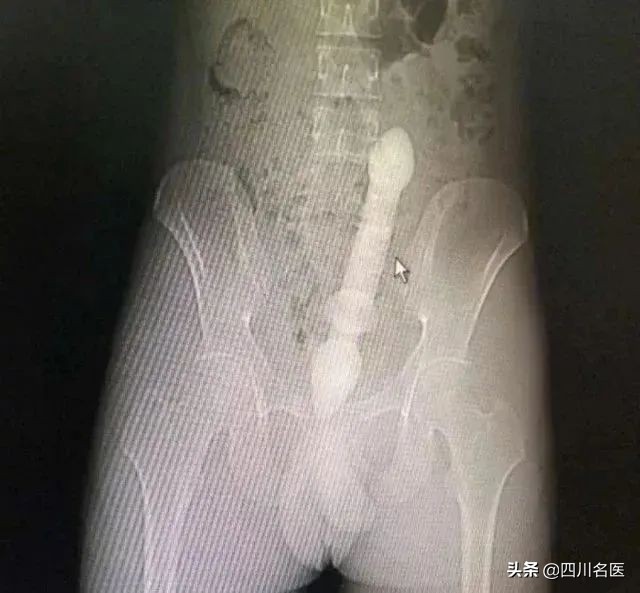

医生会通过一系列检查如直肠指诊、X线来确定体内的异物是什么,在什么位置,这一点非常关键,因为只有搞清楚里面的真实情况,医生才能找到合适的方法把异物取出。